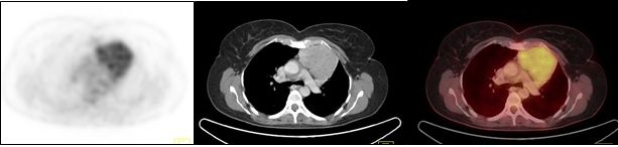

Los timomas de bajo grado (fig. 2) se caracterizaron por ser tumores bien delimitados, con estructura interna heterogénea, sin invasión a la grasa o estructuras adyacentes; presentaron hipermetabolismo leve a moderado, con un SUVmax promedio de 4,3 (rango 3,3 a 5,5) y en 2/5 hubo circulación colateral periférica.